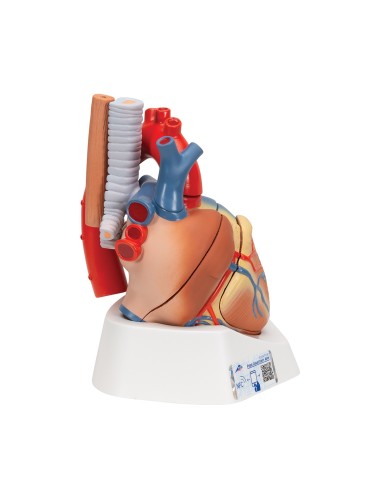

Fra i modelli di base segnaliamo il modello di cuore classico in due parti, in cui le due metà del cuore sono tenute insieme da potenti magneti.

Inoltre nella categoria sono presenti anche i modellini anatomici di cuore con bypass e con sistema di conduzione, fino ai modelli anatomici comparativi di patologie del cuore.

Per una migliore comprensione delle strutture anatomiche del cuore sono stati realizzati anche dei modelli anatomici di cuore ingrandito, si va dai piccoli ingrandimenti fino ai modelli di cuore per la formazione in aula, come il modello anatomico di cuore gigante prodotto da 3B Scientific: un modello di cuore ingrandito di ben otto volte.